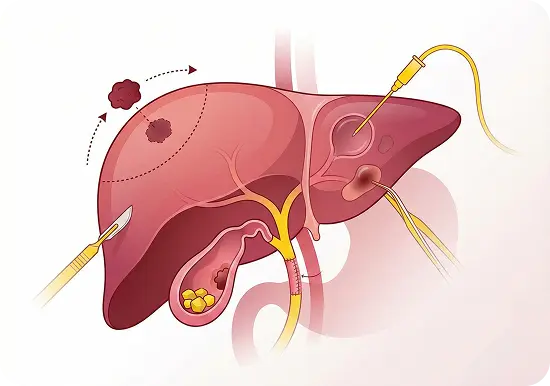

Biliary & Liver Surgery

- Hepatectomy for liver tumours and metastases

- Bile duct resections and reconstructions

- Surgery for bile duct injuries, strictures, and gallbladder stones

- Management of gallbladder cancer

- Liver cyst and abscess drainage procedures